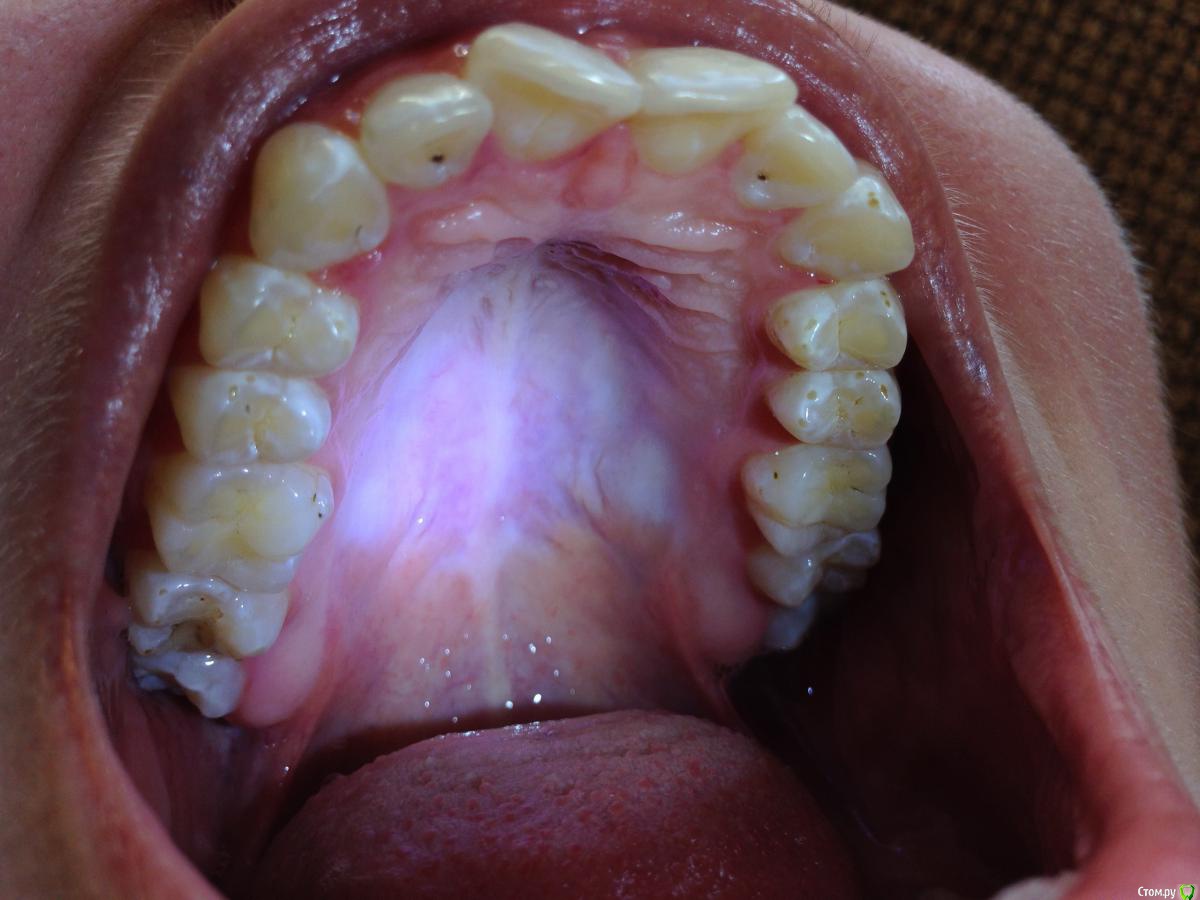

Ситуация следующая: сколько себя помню, всегда на зубах были белые пятна. Сейчас белые пятна почти на всех зубах и местами коричневые. Я не помню, когда появились коричневые пятна и очень беспокоюсь, что состояние эмали может в дальнейшем ухудшиться.

Врачи, у которых я консультировалась ставят разные диагнозы: флюороз, гипоплазия эмали. Рекомендуют наблюдаться и, к сожалению, не могут дать никаких прогнозов о развитии заболевания.

Фото зубов и снимок прилагаю. Буду очень благодарна за ваше профессиональное мнение.

Это у вас гипоплазия эмали вследствии флюороза, или так называемые крапчатые зубы. Что делать?, Ничего страшног просто участки с поврежденной эмалью очень хрупкие и поэтому выкрашиваются, просто пломбируйте, зато у вас устойчивостьт к кариесу повышенная